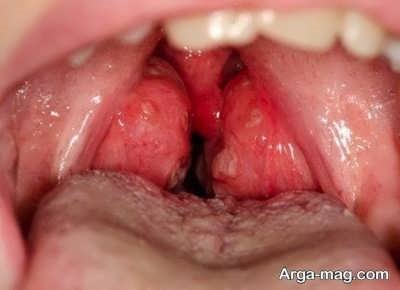

- در واقع شما به راحتی و با نگاه کردن در آینه می توانید این بیماری را تشخیص دهید و کافی است دهان خود را باز کرده و حروف آ را مرتب تکرار کنید.

- شما زمانی که این کار را انجام می دهید باعث خواهید شد تا لوزه هایی که پشت گلوی شما می باشند به راحتی دیده شوند.

- اگر این لوزه ها قرمز ملتهب بود باید بدانید که به این بیماری دچار شده اید.

- معمولا ویروسها و باکتری ها منجر به ایجاد این بیماری می شوند و اگر علاوه بر التهاب روی لوزه های خود لکه های قرمز ریز را مشاهده کردید باید در نظر داشته باشید که این مورد را ویروس اپشتین ایجاد کرده است.